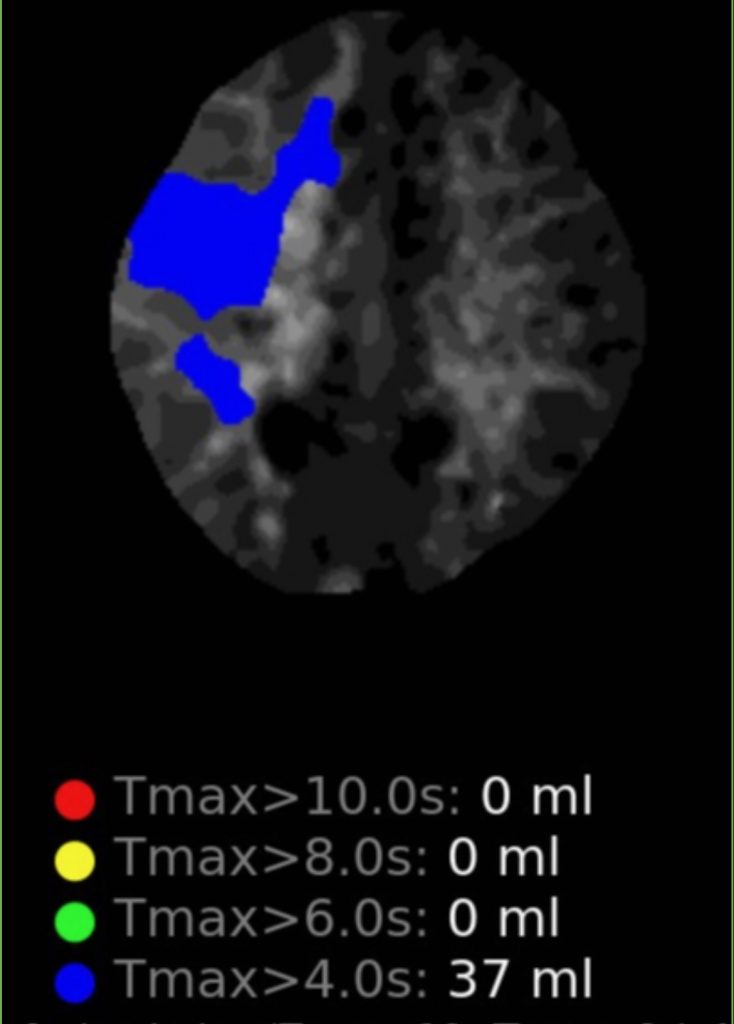

Figure 1

Noninvasive vascular imaging was sufficiently suggestive to warrant conventional digital subtraction angiography, performed by Dr. Brisman and confirming Moya-Moya syndrome (Figures 1). CT Perfusion (Figure 2) showed a decreased transit time of blood to the right hemisphere and the patient was recommended to undergo cerebral revascularization to avert stroke.